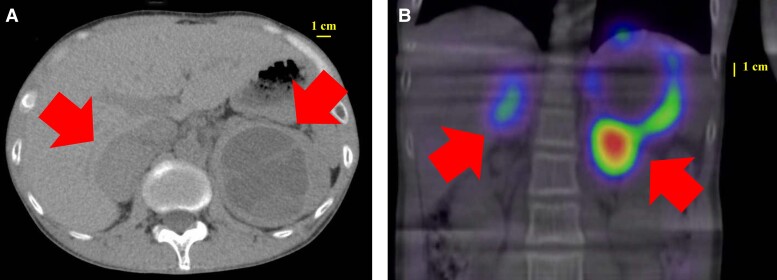

男性,37岁,过去一年出现多尿和体重下降的症状。初步实验室检查显示血糖升高(468 mg/dL [25.9 mmol/L];正常参考范围[RR], 75-109 mg/dL [4.1-6.0 mmol/L]),高糖化血红蛋白A1c (13.2% [120 mmol/mol];RR为4.6 ~ 6.2% [26 ~ 44 mmol/mol]),尿c肽排泄量低(17.4 μg/day [5.76 nmol/day];RR为18.3 ~ 124.4 μg/day [6.0 ~ 41.1 nmol/day]),伴有酮症,诊断为胰岛素依赖型糖尿病。随后的调查确定了甲状腺髓样癌和双侧嗜铬细胞瘤。结合检测到RET基因变异及患者多发性内分泌瘤2A型(MEN2A)家族史,确认MEN2A的诊断。入院后,开始强化胰岛素治疗,症状得到缓解,血糖水平恢复正常。随后行腹腔镜双侧肾上腺切除术,术后患者糖耐量恢复正常,无需糖尿病治疗,避免低血糖。该病例强调了儿茶酚胺通过α2作用于胰腺β细胞诱导的胰岛素分泌抑制的潜力,在MEN2A患者经历胰岛素依赖型糖尿病的肾上腺切除术后得到缓解和迅速改善。

A 37-year-old man presented with symptoms of polyuria and weight loss over the past year. Initial laboratory examination showed elevated blood glucose level (468 mg/dL [25.9 mmol/L]; normal reference range [RR], 75-109 mg/dL [4.1-6.0 mmol/L]), high glycated hemoglobin A1c (13.2% [120 mmol/mol]; RR, 4.6-6.2% [26-44 mmol/mol]), low urinary C-peptide excretion (17.4 μg/day [5.76 nmol/day]; RR, 18.3-124.4 μg/day [6.0-41.1 nmol/day]), and ketosis, leading to a diagnosis of insulin-dependent diabetes mellitus. Subsequent investigations identified medullary thyroid carcinoma and bilateral pheochromocytomas. Given the detected RET gene variant and the patient's family history of multiple endocrine neoplasia type 2A (MEN2A), the diagnosis of MEN2A was confirmed. Upon hospital admission, intensive insulin therapy was commenced, which resolved the symptoms and normalized blood glucose levels. Subsequently, laparoscopic bilateral adrenalectomy was performed, after which the patient's glucose tolerance normalized, eliminating the need for diabetes treatment and avoiding hypoglycemia. This case highlights the potential for catecholamine-induced suppression of insulin secretion via α2 action on pancreatic β-cells to be remission and rapidly improved by adrenalectomy in individuals with MEN2A experiencing insulin-dependent diabetes mellitus.